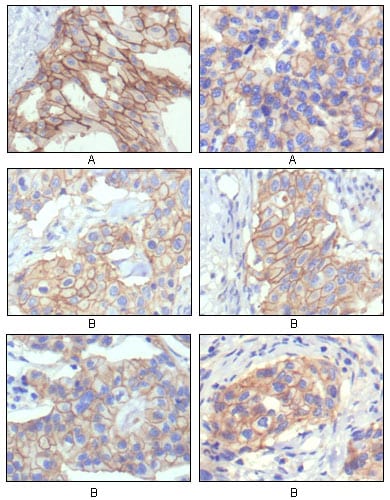

分类: 科研抗体货号: 20127别名: HER-2, C-erB-2, erbB-2应用: IHC反应种属: Human